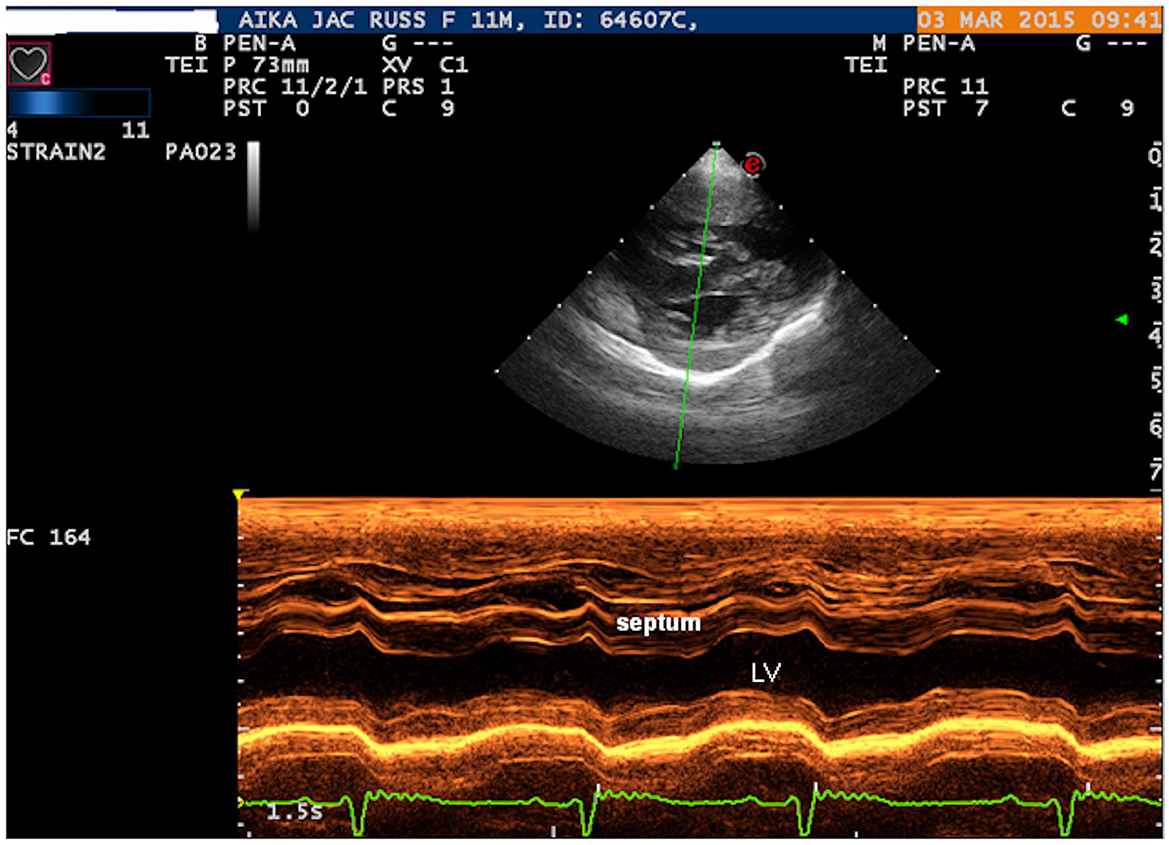

La ecocardiografía bidimensional (Philips Ultrasound EPIQ Elite, Philips S.p.A.) mostró una comunicación interventricular media, aislada y de gran tamaño (7 mm) (Figura 1, Videos Suplementarios S1, S2). La proyección del eje corto paraesternal derecho, a nivel de los músculos papilares del ventrículo izquierdo, mostró hipertrofia de la pared del ventrículo derecho (1 cm) y aplanamiento sistólico del tabique interventricular, sin estenosis pulmonar (Figura 2). El Doppler de flujo de color reveló una derivación bidireccional a través del VSD grande (Figura 1). La ausencia de regurgitación pulmonar o tricuspídea impidió la estimación de la presión arterial dentro de la circulación pulmonar y los propietarios no dieron su consentimiento para el cateterismo pulmonar sugerido para medir directamente la presión de la arteria pulmonar. No se encontraron otras cardiopatías congénitas asociadas a la comunicación interventricular.